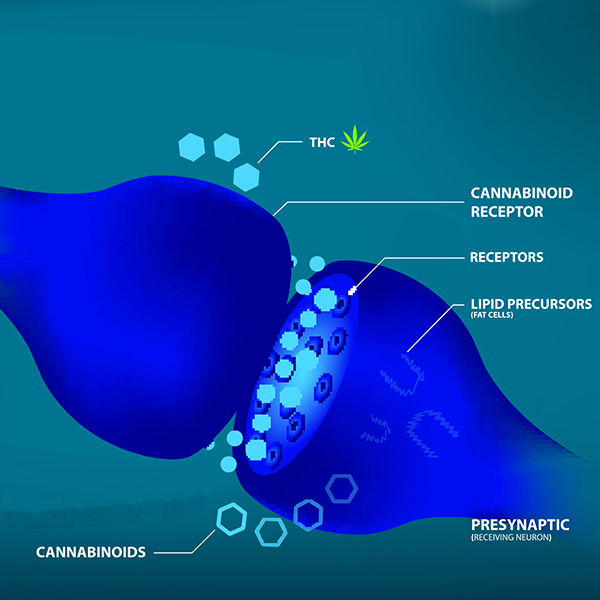

Waarom wordt CBD bij de hond en de kat gebruikt?